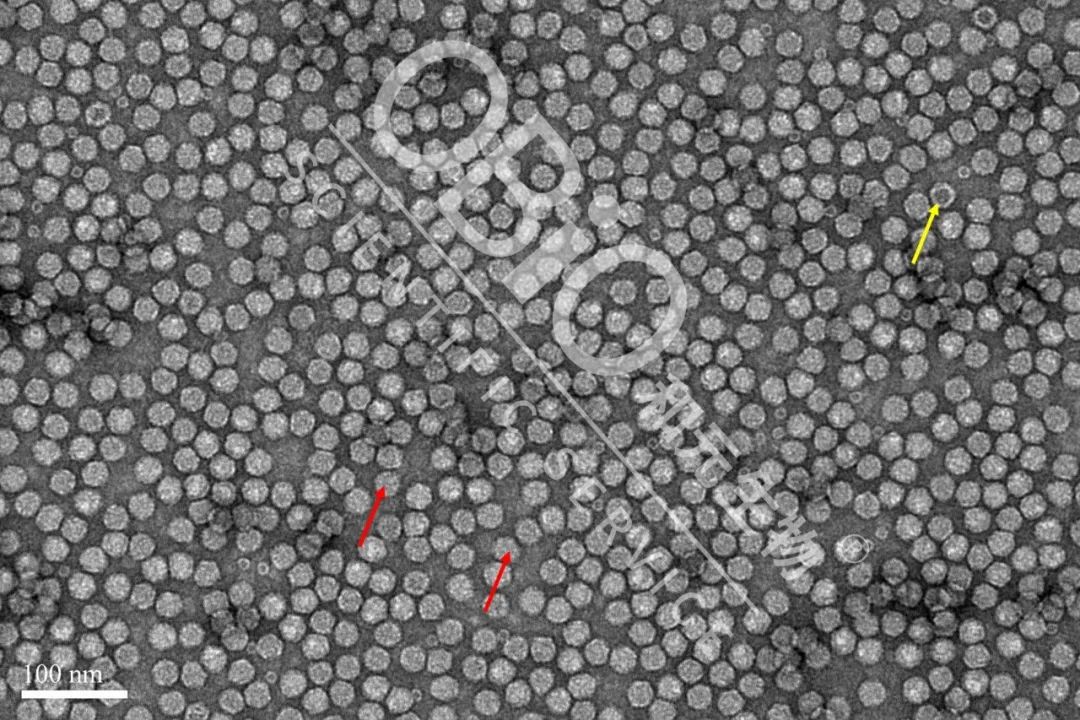

图2 中国-九游·会J9官方网站|真人游戏第一品牌 rAAV载体生产空壳率

电镜结果:包装DNA基因组的病毒颗粒为实心颗粒(红色箭头);空病毒颗粒中间存在空洞(黄色箭头)